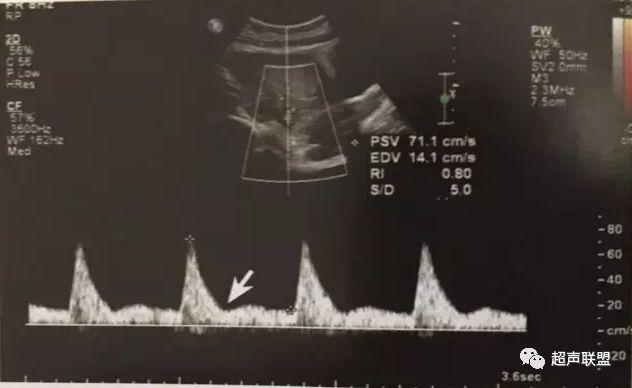

图2 脐动脉舒张期血流消失或反向

缺氧首先出现的变化是舒张末期血流降低,S/D值、RI值和PI值升高。当缺氧进入再分配晚期时,可逐渐出现舒张期血流减少、舒张期血流缺失。失代偿期出现脐动脉血液逆流,舒张期血流倒置。

2、脐动脉标准:孕30周后,S/D>3;晚孕期,RI >0.75;孕18~20周后,脐动脉舒张期缺如或反向(后者见于严重的宫内缺氧者);

1、脐动脉舒张期血流信号消失或反向;